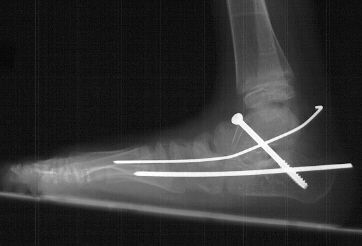

Some mechanism has to be used to correct the hindfoot valgus.. That was the case in this child in which subtalar arthrodesis with autograft bone graft and screw fixation was performed.